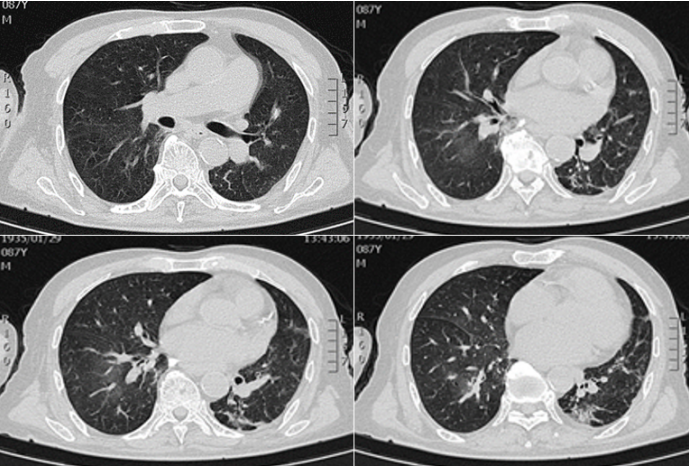

胸部CT:双肺轻度间质渗出,左肺斑片状渗出伴实变,左侧胸腔积液,左房、左室增大1

图1  患者入院时胸部CT